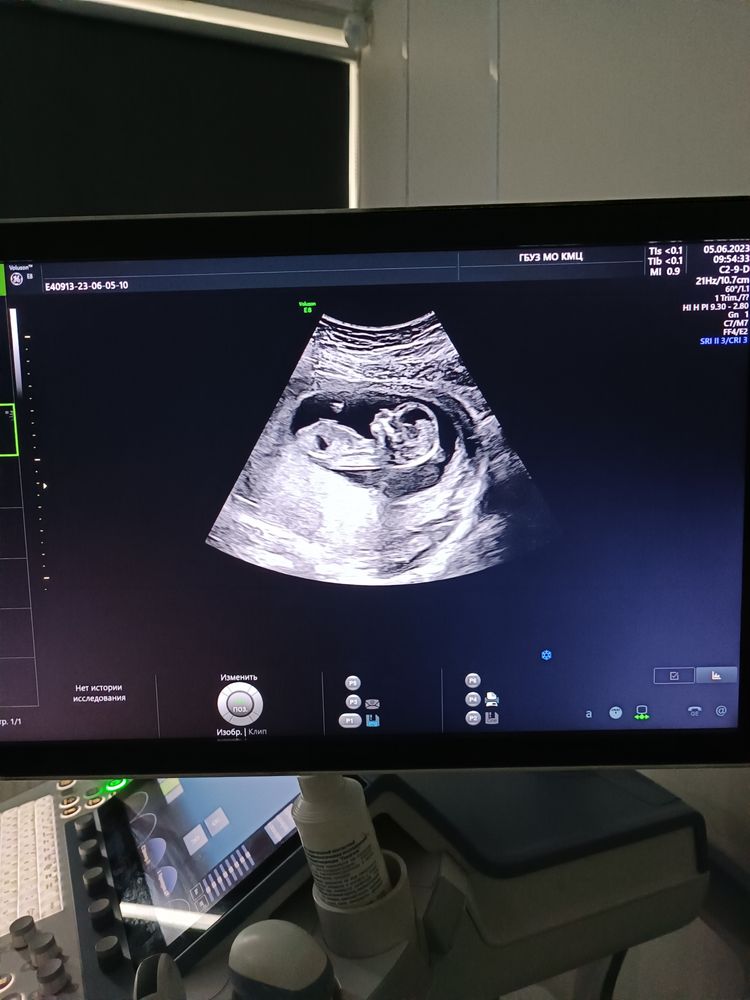

1 скрининг, двойня 💞

Вот теперь мы стали моно ди 😊

Риски минимальные, один малыш срок в срок 13,5

Второй малыш поменьше 13,1